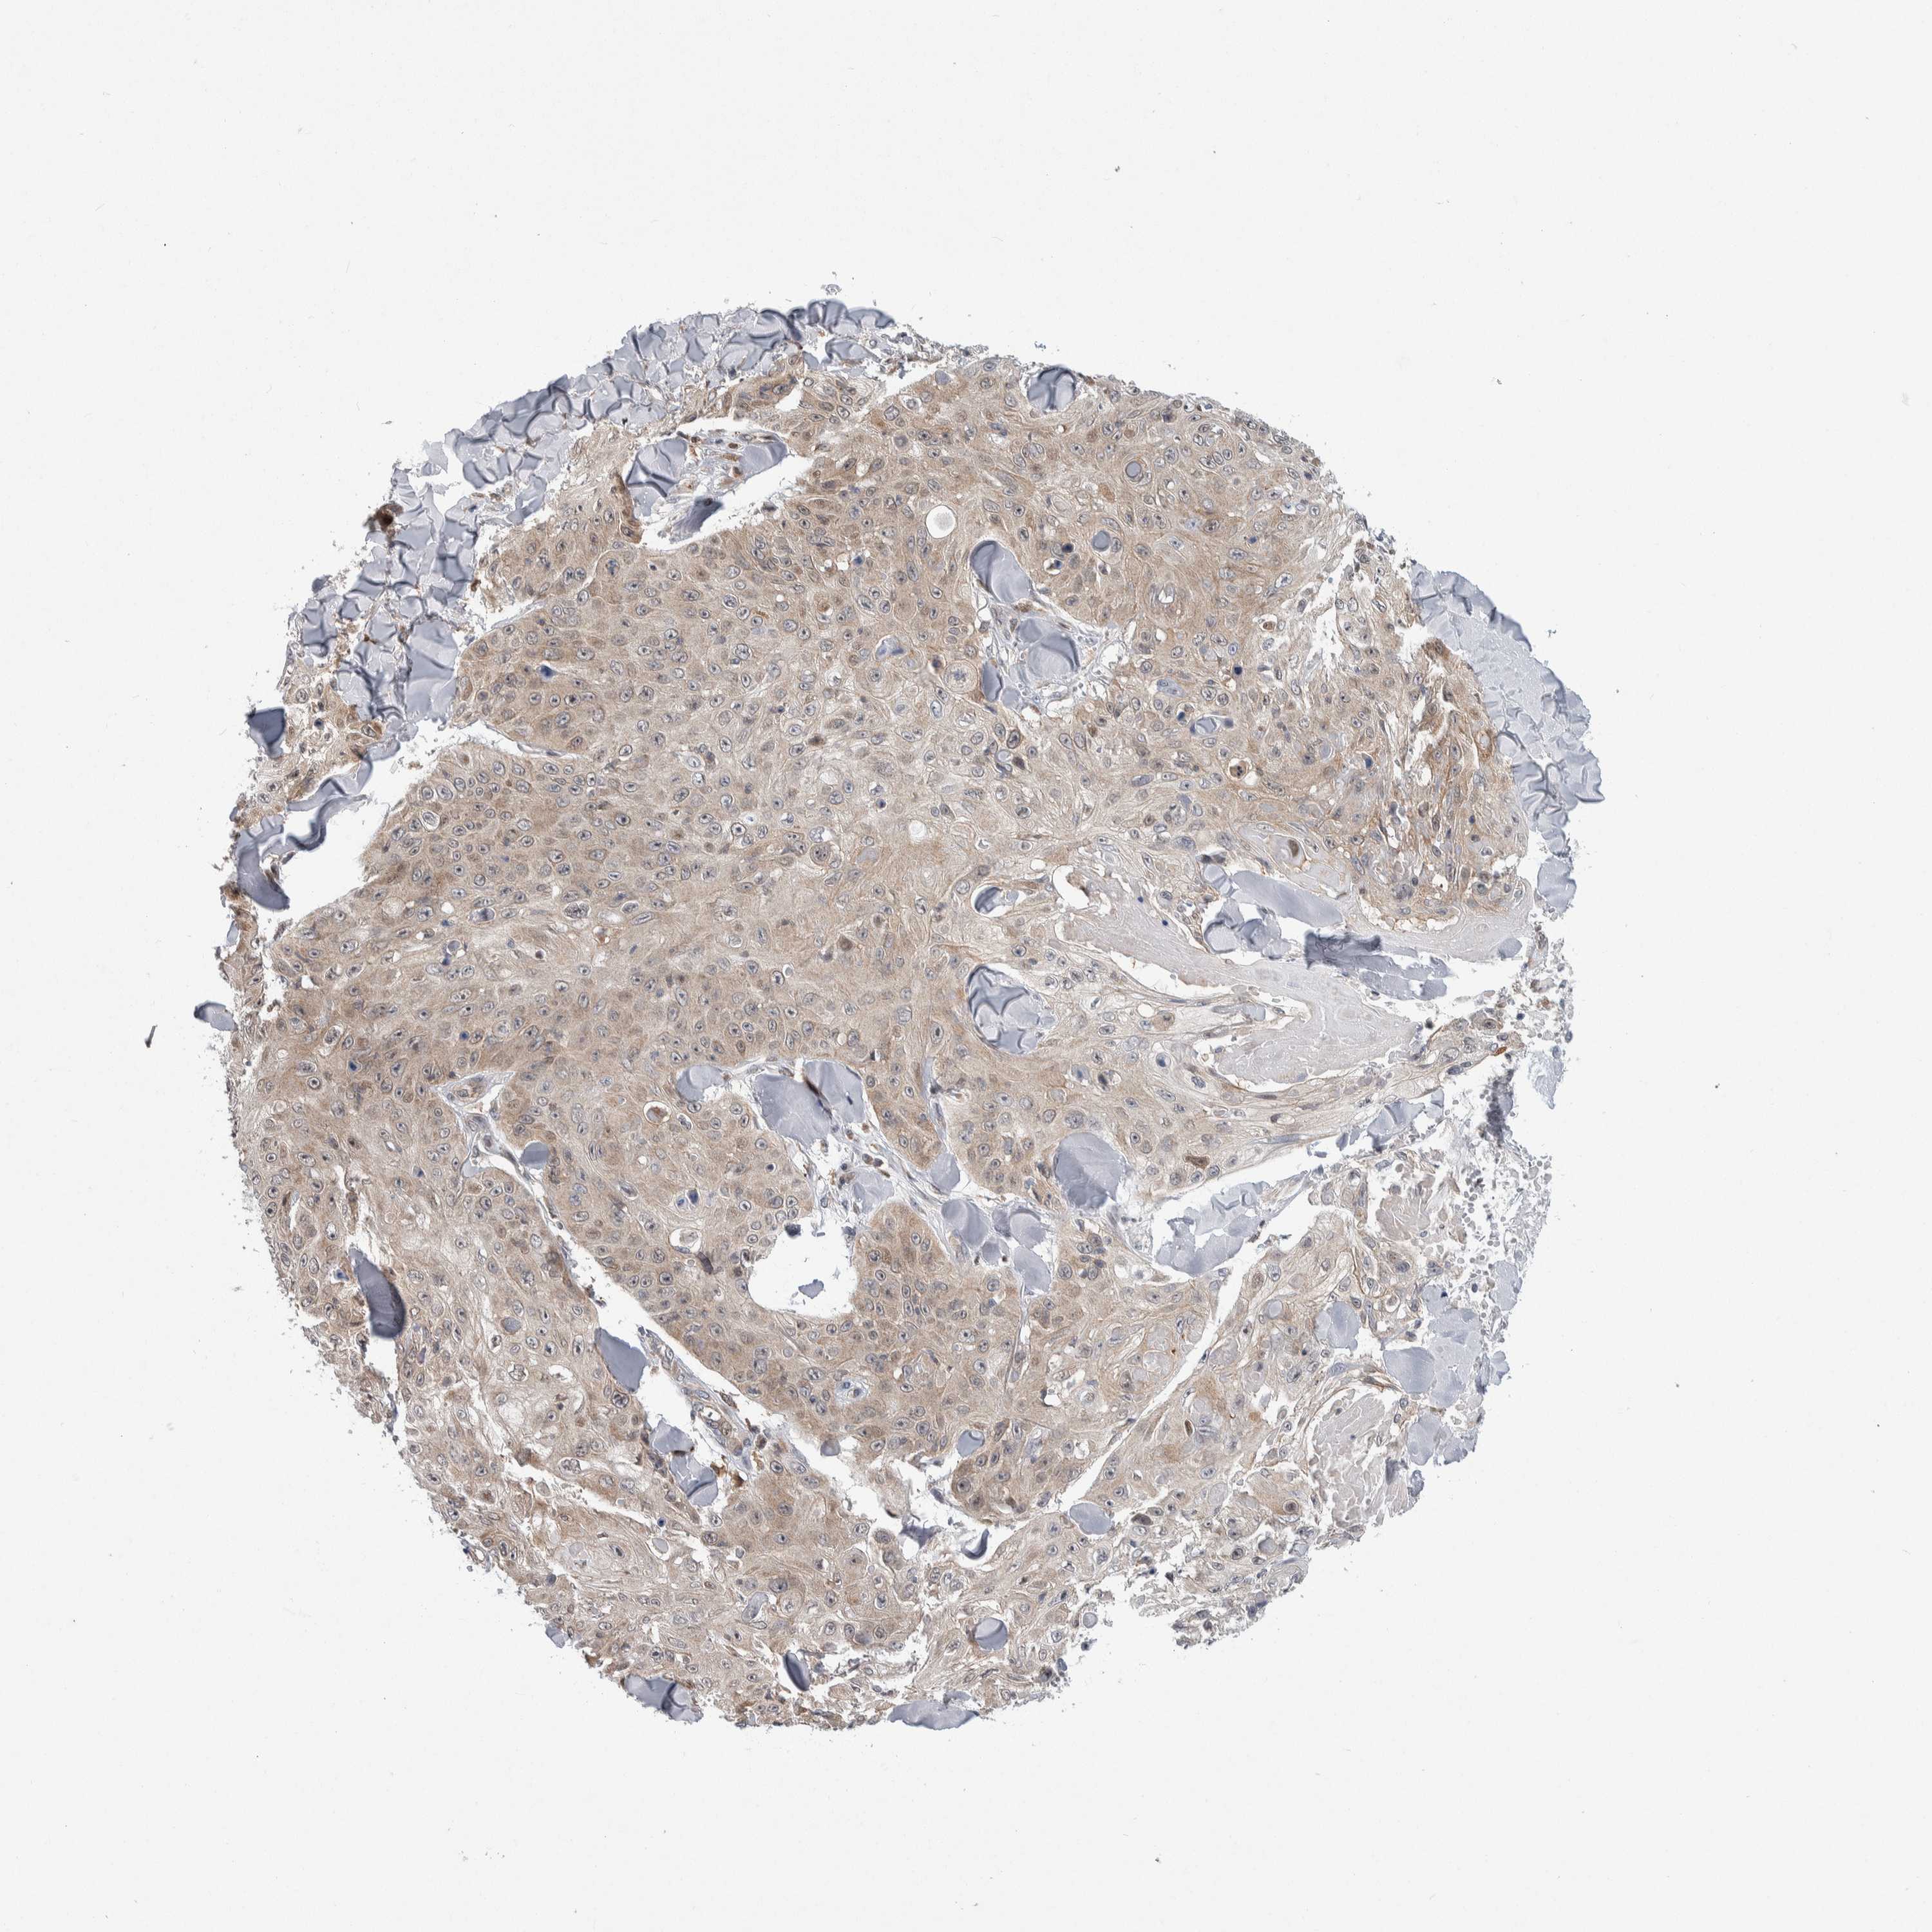

SKIN CANCER - Protein expressioni

A mouse-over function shows sample information and annotation data. Click on an image to view it in a full screen mode. Samples can be filtered based on level of antibody staining by selecting one or several of the following categories: high, medium, low and not detected. The assay and annotation is described here.

Antibody stainingi

Antibody staining in the annotated cell types in the current human tissue is reported as not detected, low, medium, or high, based on conventional immunohistochemistry profiling in selected tissues. This score is based on the combination of the staining intensity and fraction of stained cells.

Each image is clickable and will lead to virtual microscopy that enables deeper exploration of all samples and also displays staining intensity scores, fraction scores and subcellular localization as well as patient and tissue information for each sample.

HPA005695

Staining

High

Medium

Low

Not detected

Intensity

Strong

Moderate

Weak

Negative

Quantity

>75%

75%-25%

<25%

None

Location

Nuclear

Cytoplasmic/membranous

Cytoplasmic/membranous,nuclear

Squamous cell carcinoma, NOS